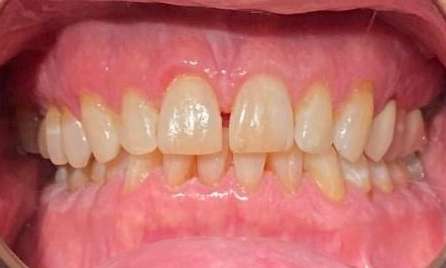

She came to us with a deep bite due to her lower front teeth sitting too high and her two front teeth pushed forward. Using Invisalign, we moved her lower front teeth down into their proper position and pulled the two front teeth back into place. She also needed a deep cleaning to removed deep buildup and restore her gum health. The results are beautiful and healthy!